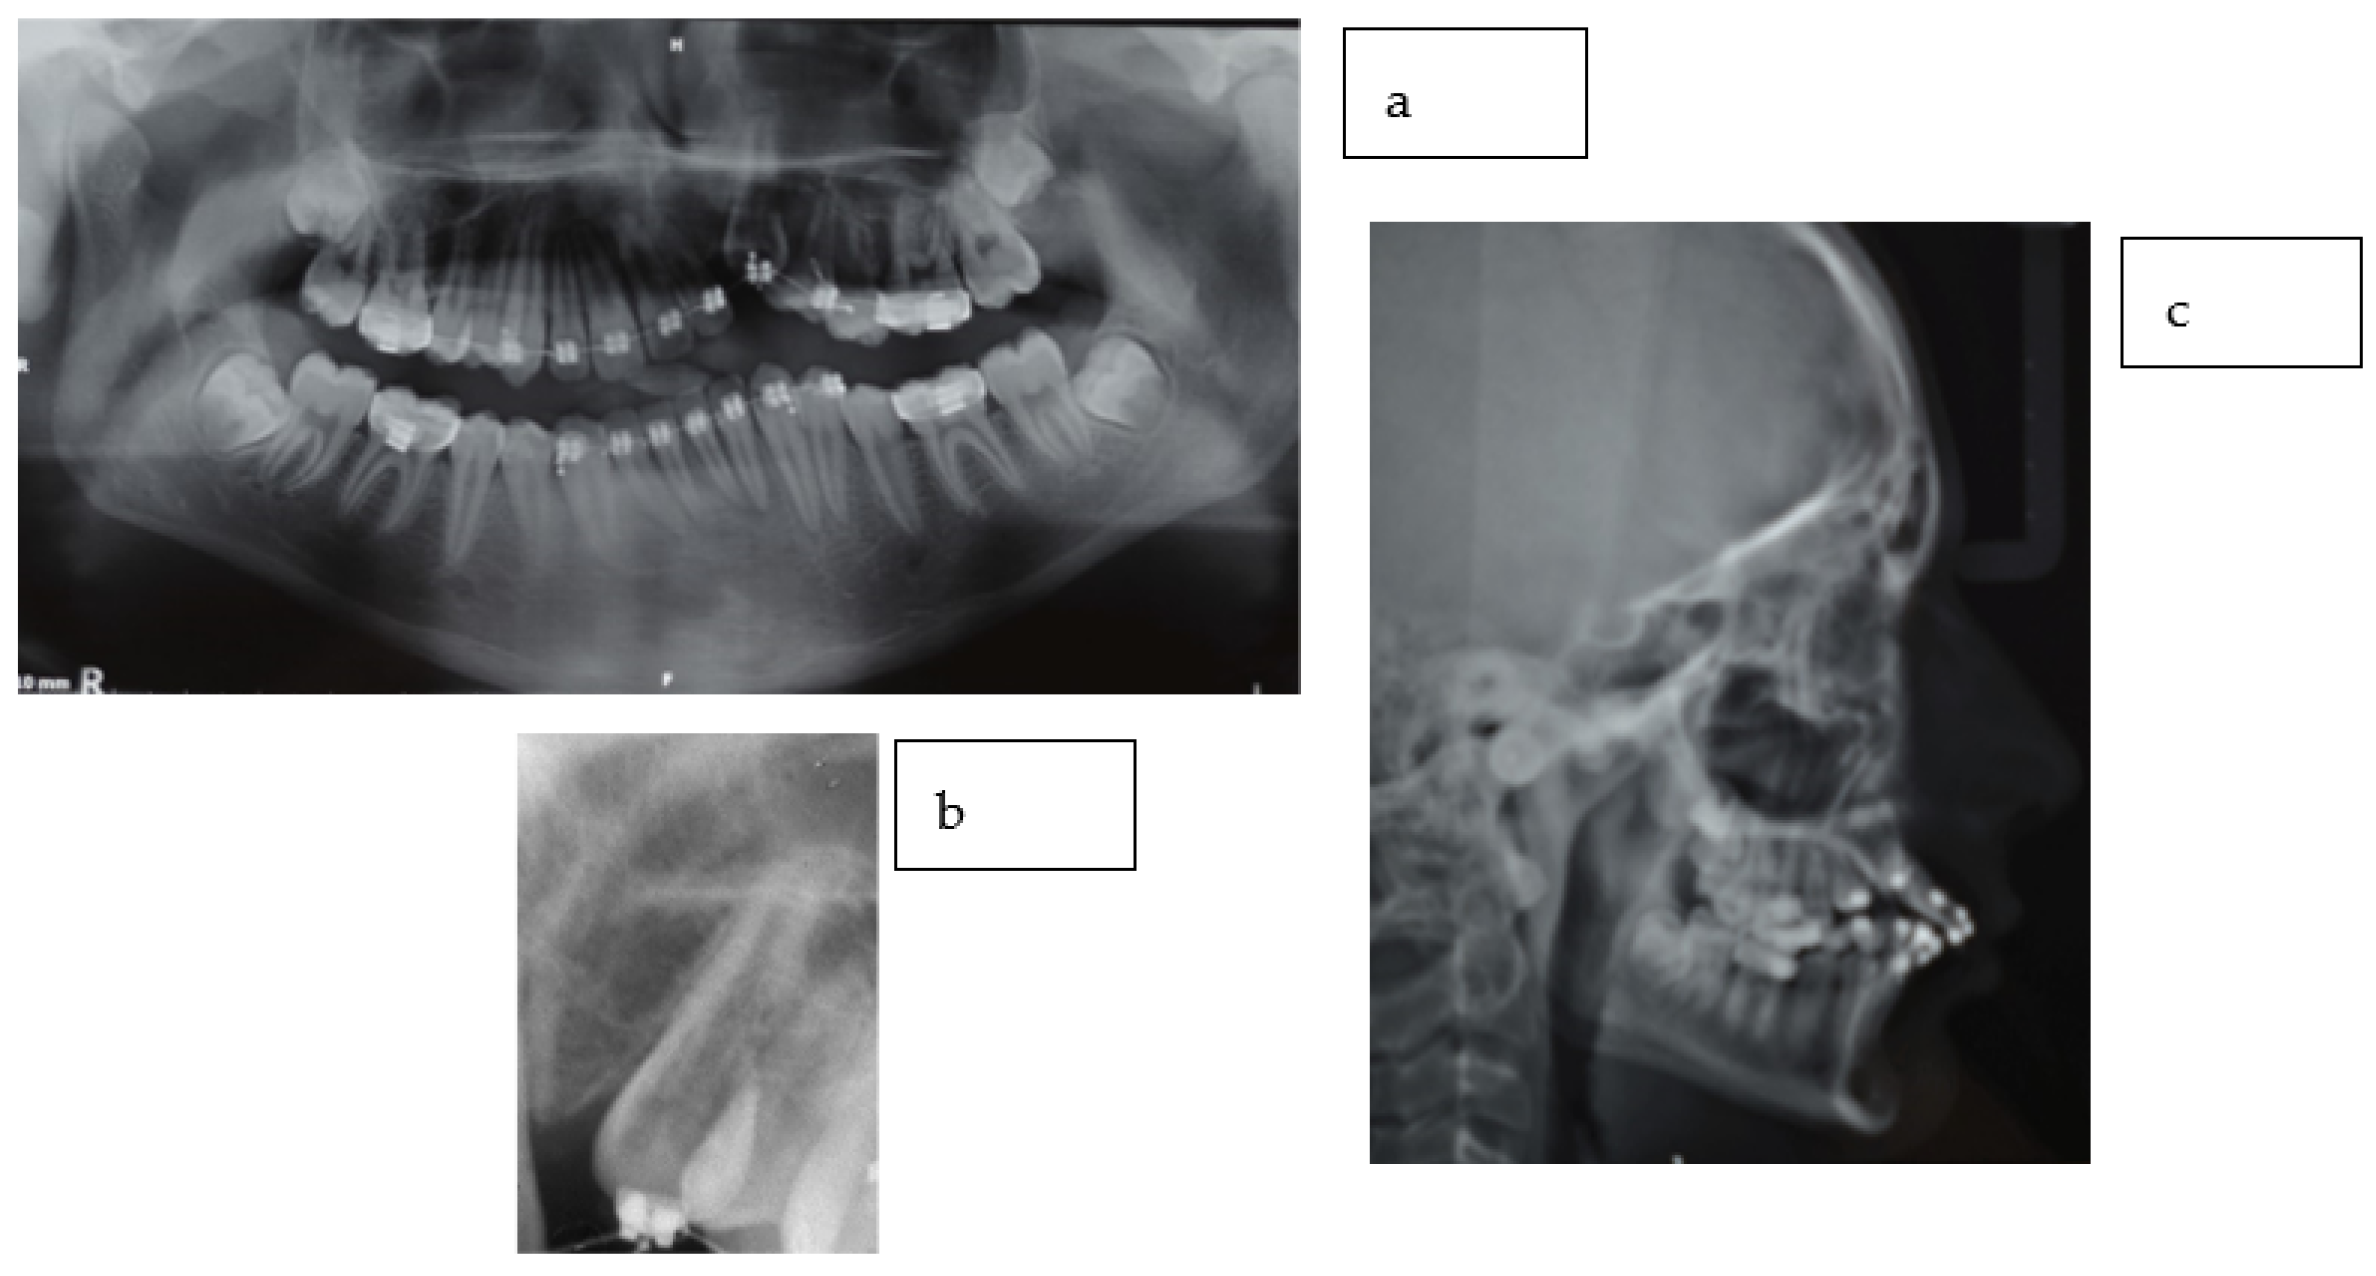

2.2. Radiographic Findings

2.3. Diagnostic Assessment